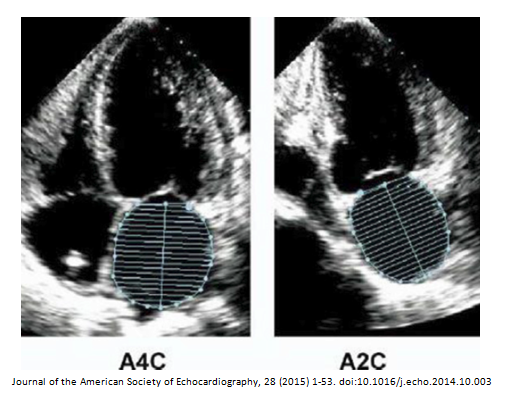

Simpsons BIPLANE method

4 chamber view

-systole and diastole

-do not include papillary or trabeculations

2 chamber view

LVEF = LVEDV – LVESV / LVEDV

LV biplane measurement

Straight line at MV level-height from midpoint Do NOT include papillary muscles or trabelculations No forshortening LV length perpendicular to base